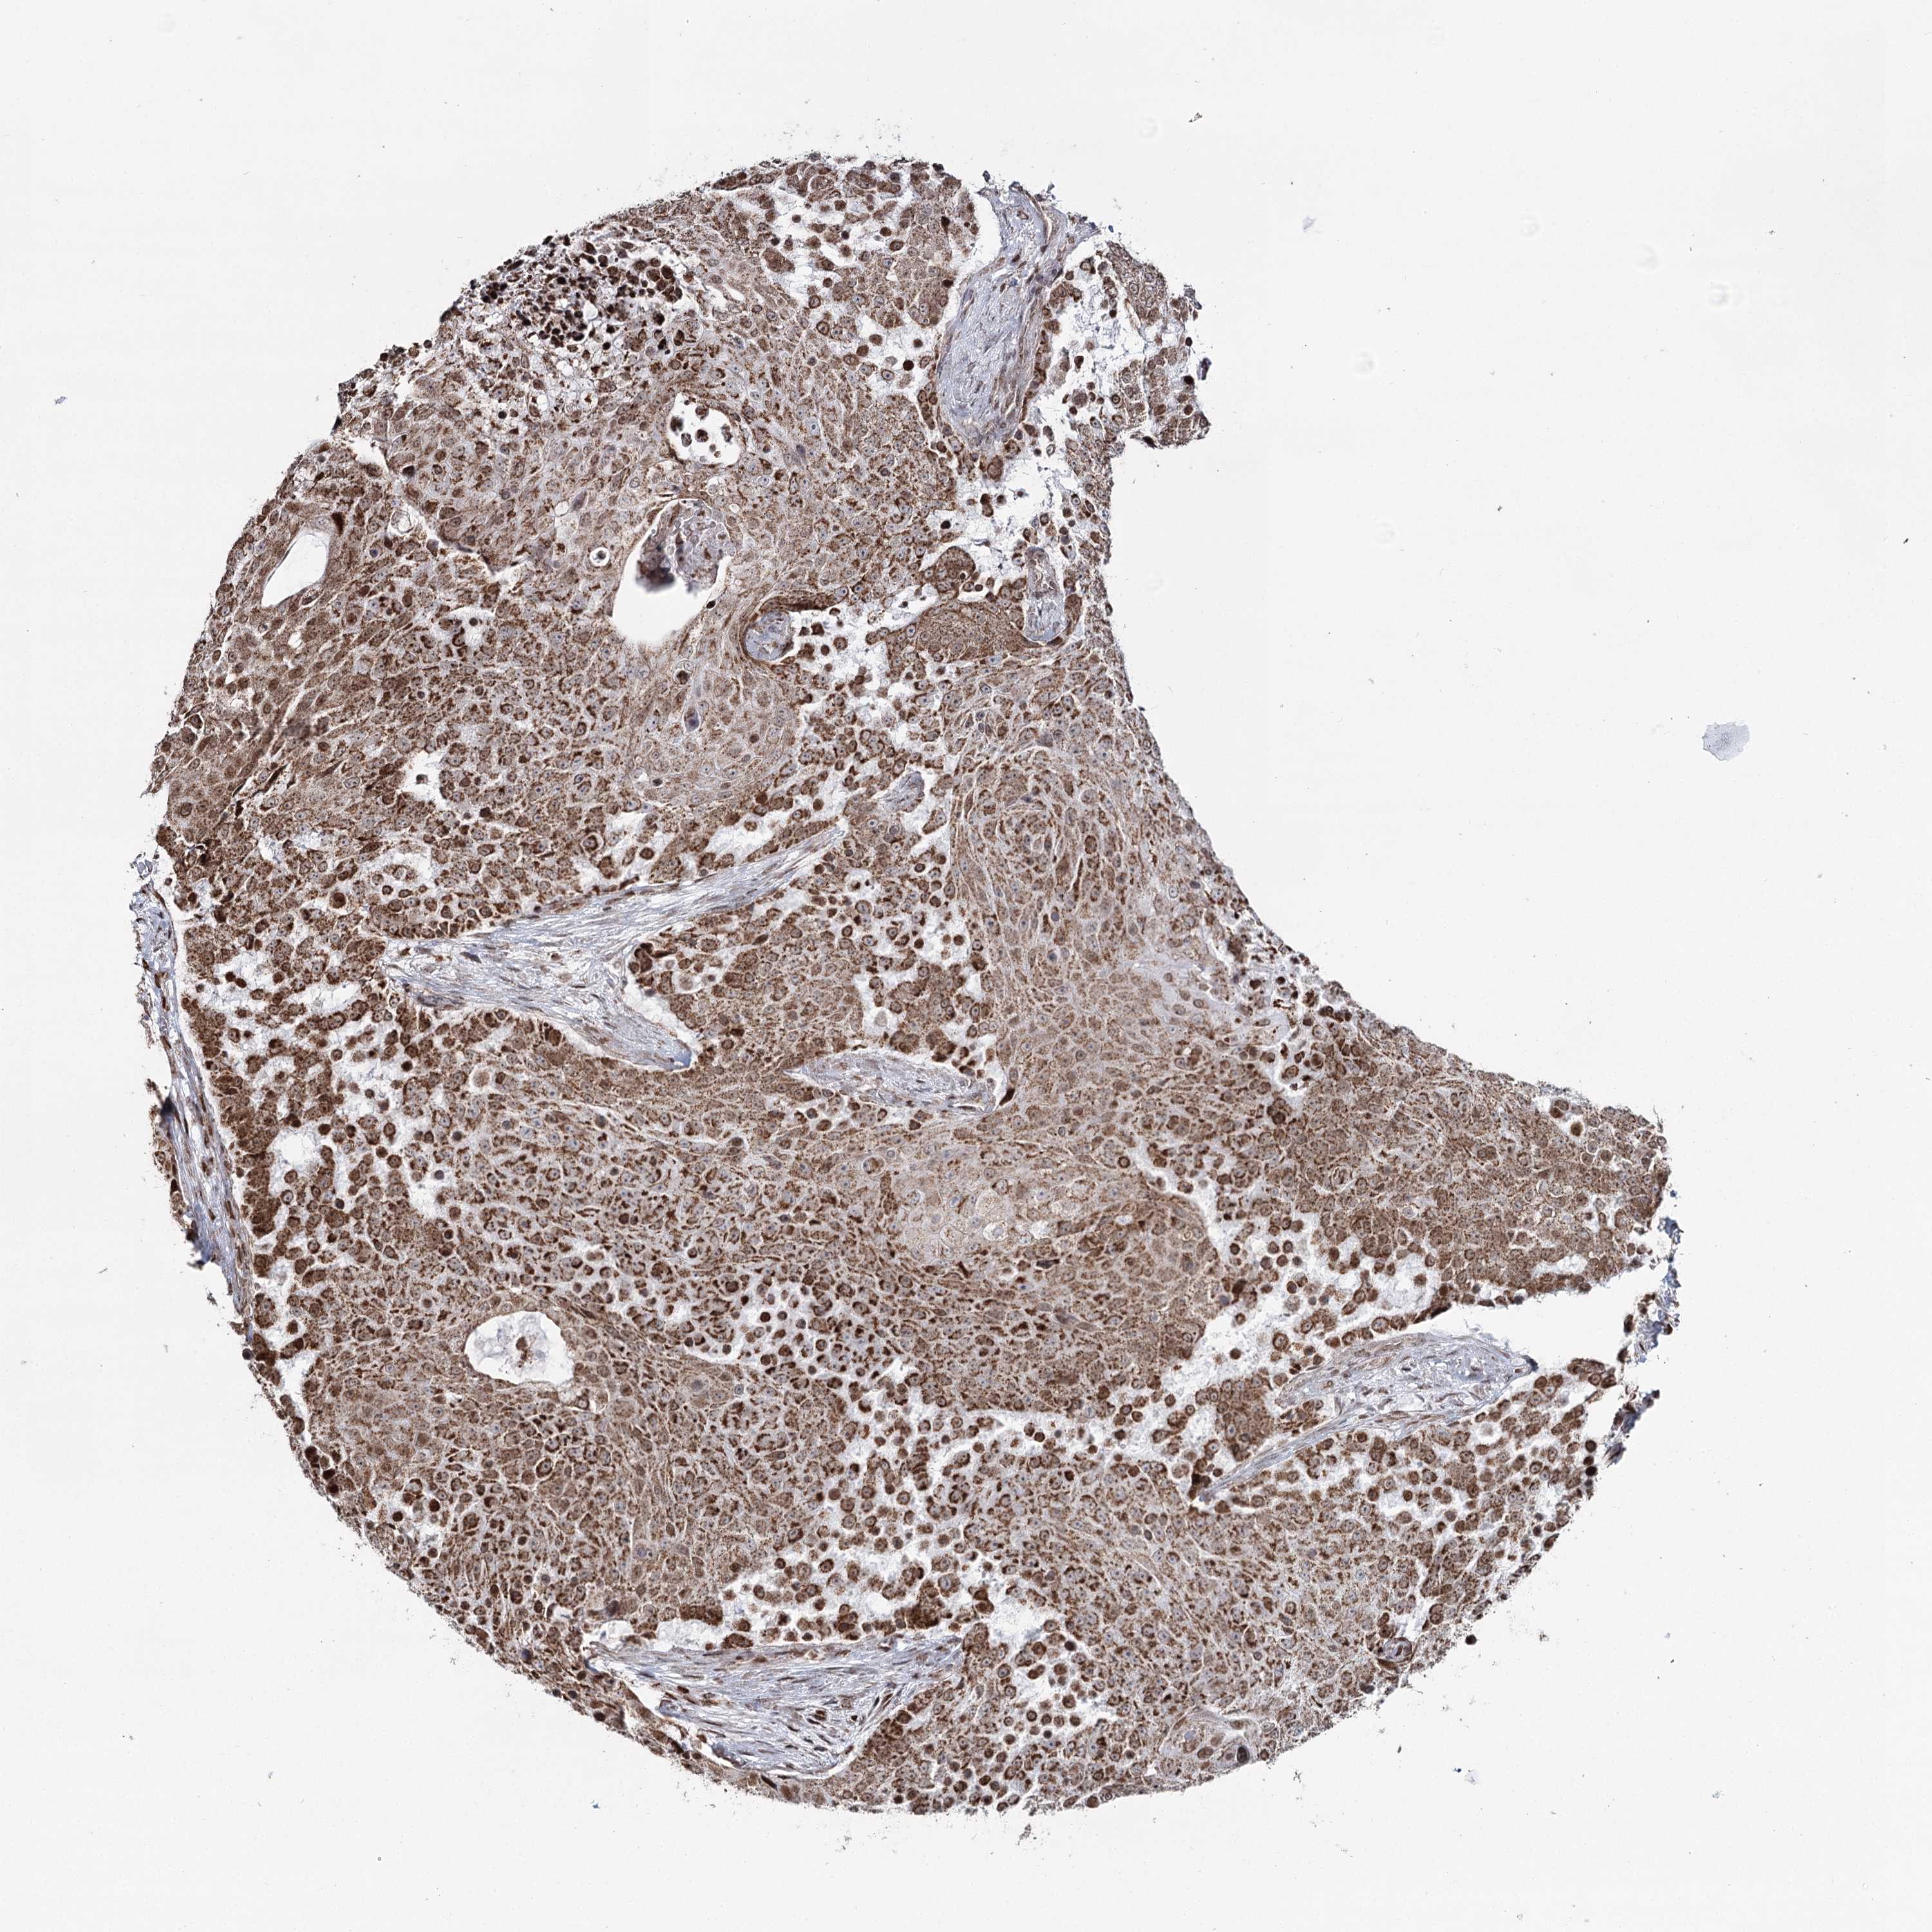

UROTHELIAL CANCER - Protein expressioni

A mouse-over function shows sample information and annotation data. Click on an image to view it in a full screen mode. Samples can be filtered based on level of antibody staining by selecting one or several of the following categories: high, medium, low and not detected. The assay and annotation is described here.

Antibody stainingi

Antibody staining in the annotated cell types in the current human tissue is reported as not detected, low, medium, or high, based on conventional immunohistochemistry profiling in selected tissues. This score is based on the combination of the staining intensity and fraction of stained cells.

Each image is clickable and will lead to virtual microscopy that enables deeper exploration of all samples and also displays staining intensity scores, fraction scores and subcellular localization as well as patient and tissue information for each sample.

Antibody HPA038484

Antibody HPA038485

Staining

High

Medium

Low

Not detected

Intensity

Strong

Moderate

Weak

Negative

Quantity

>75%

75%-25%

<25%

None

Location

Nuclear

Cytoplasmic/membranous

Cytoplasmic/membranous,nuclear

Urothelial carcinoma, High grade

Urothelial carcinoma, Low grade

Urothelial carcinoma, NOS